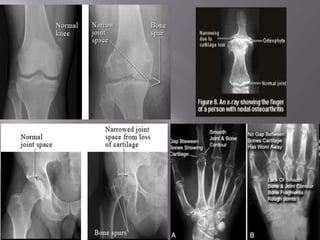

Diagnosis – Radiography

X-Rays are indicated to evaluate chronic hand

pain and hip pain thought to be due to OA

For knee pain, X-Ray should be obtained if

symptoms or signs are not typical of OA or

Pain persists after inauguration of effective

treatment

Radiographic Features

Erosion

Bone Cyst

Subchondral Sclerosis

Osteophytes

Narrow Joint Space